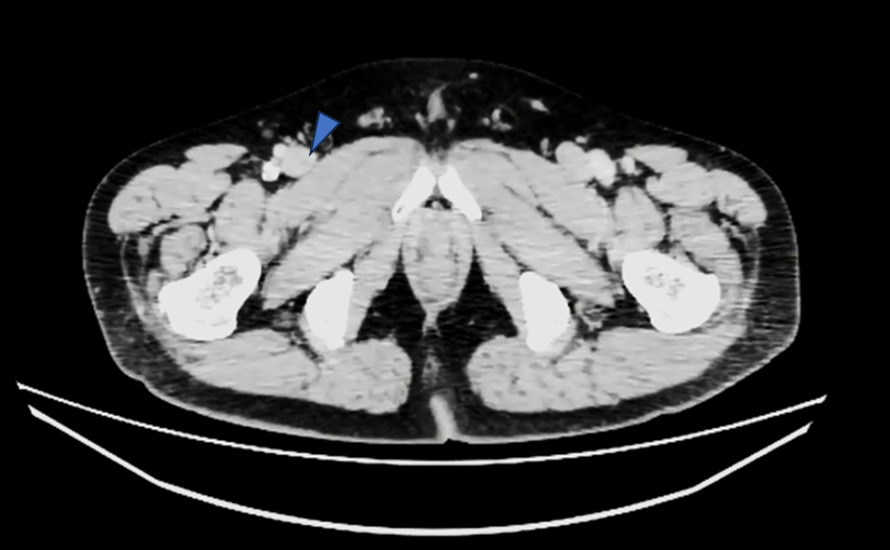

冠動脈に有意な狭窄はなかったのですが、先ほどの症例と同じように

肺動脈にfillifng defectを認めます。

造影後”15分後”に追加で撮影した画像がこちらです。

造影後15分後でも造影効果がわずかに残っていました。

これを見ると、冠動脈CTでは右肺動脈に大きい血栓があるように見えましたが、左肺動脈の方が血栓サイズが大きく、これによる左胸の痛み症状だったのではないかと考えられました。

下肢静脈も15分後でもわずかに造影効果が残っており、左浅大腿静脈にfilling defectを認めました。

造影剤量も60mlと通常の深部静脈を観察するには少ない量でしたが、15分後の撮影でもなんとか観察することができました。

こちらも管電圧を下げて撮影しました。時間経過で造影効果が低くなった肺動脈や深部静脈の造影効果を上げてなんとか観察することができた症例です。